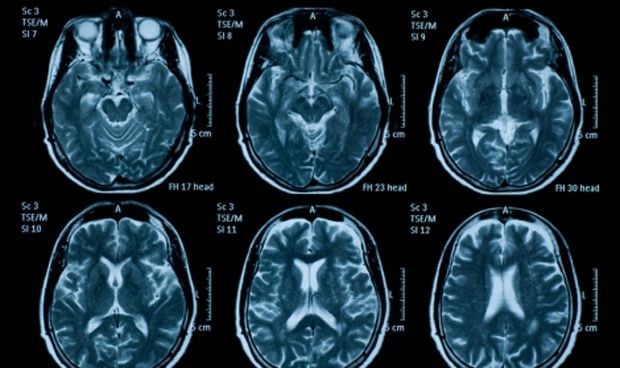

En el estudio se incluyeron un total de

271 estudios publicados y pre-publicados que informaron al menos de un caso de

cualquier manifestación neurológica de nueva aparición asociada temporalmente con la vacunación por SARS-CoV-2 en humanos, no explicada por otra etiología. Además, se incluyeron sujetos vacunados contra Covid-19 con cualquiera de las

vacunas disponibles.

De todos esos estudios, al final se analizaron

86 artículos, que incluyeron

13.809 pacientes que mostraron algún tipo de manifestación neurológica. Existió un

predominio femenino (63,89 por ciento), con 7.910 casos en mujeres y 4.469 en varones, de los 12.379 en los que se informó el sexo. La

mediana de edad fue de 50 años (rango: 19-97).